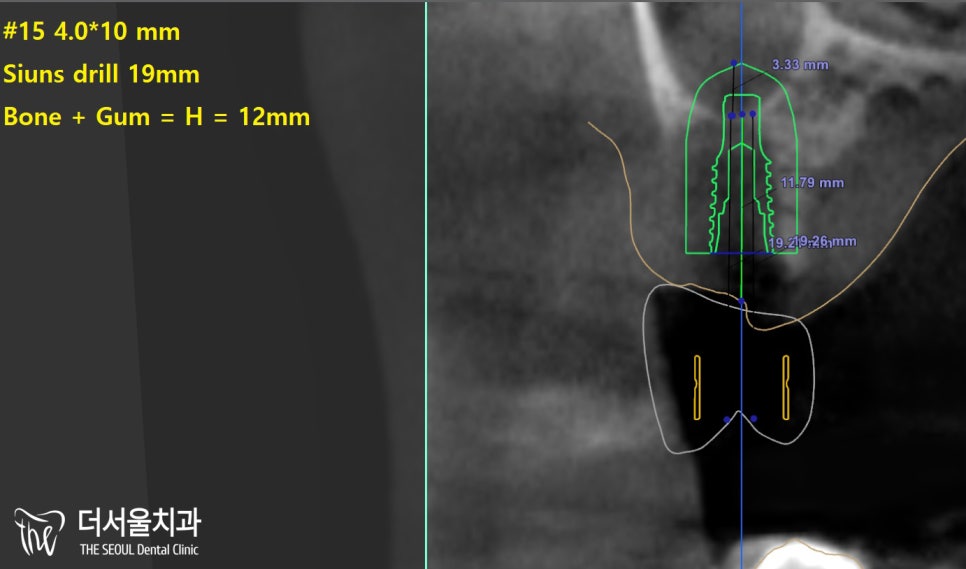

그전에 신흥역치과 는 디지털 프로그램으로

계획을 수립하기로 했습니다.

그 다음, 디지털 프로그램을 이용하는데요.

이렇게 디지털 프로그램을 이용하면,

모의로 수술을 진행해볼 수 있어 좋습니다.

어디에 무엇이 부족한지 정확히 알 수 있죠.

이를 통해 추가로 진행해야 될 것들이 있는지 볼 수 있습니다.

환자분은 뼈 자체가 좋지 않았습니다.

픽스처를 심으면 상악동 막을 뚫을 수 있죠.

그래서 뼈이식을 통해 뼈를 좀 더 채우기로 했습니다.